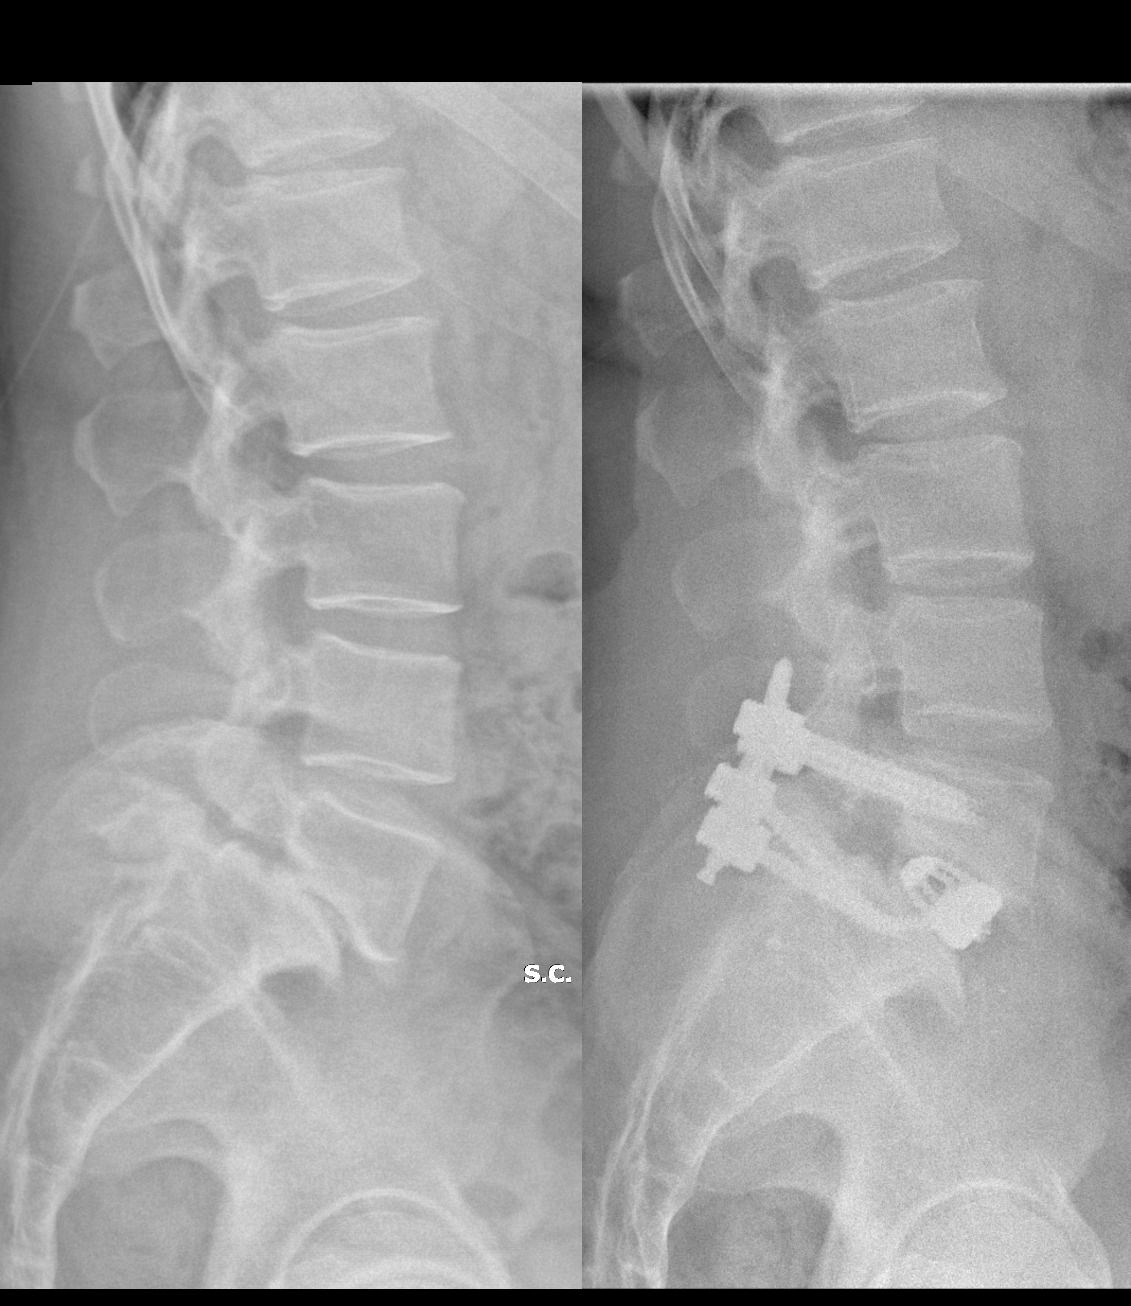

Foto e video